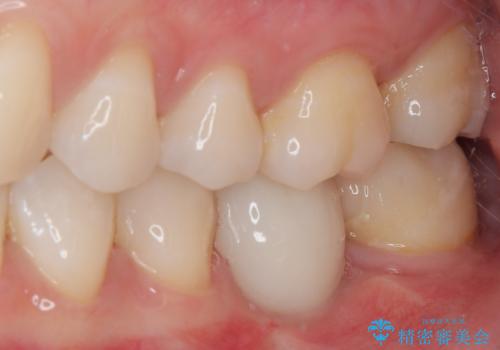

- ブリッジの歯のないところにインプラントを入れて、銀歯を白くやり替えたいと来院された患者様です。

歯の欠損している箇所にはインプラント治療をし、銀歯と仮詰めの部分はセラミックインレーにて補綴することとしました。